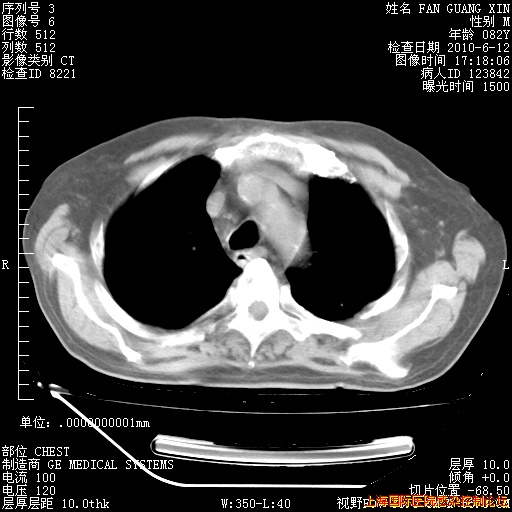

6月12日纵膈窗

整整相隔30天的肺部CT好像有所好转啊。甲强龙减量第3天,需要观察体温。

海管,自昨日你和我通完话后,不知您岳父消化道症状有无缓解?体温怎样?阅读7.12日胸部ct,个人认为目前激素治疗是有效的,甲强龙减量是适宜的。因在抗痨治疗,需密切观察肝功、肾功能和血常规。不过,老年、长期住院和大量使用激素,很担心菌群失调发生